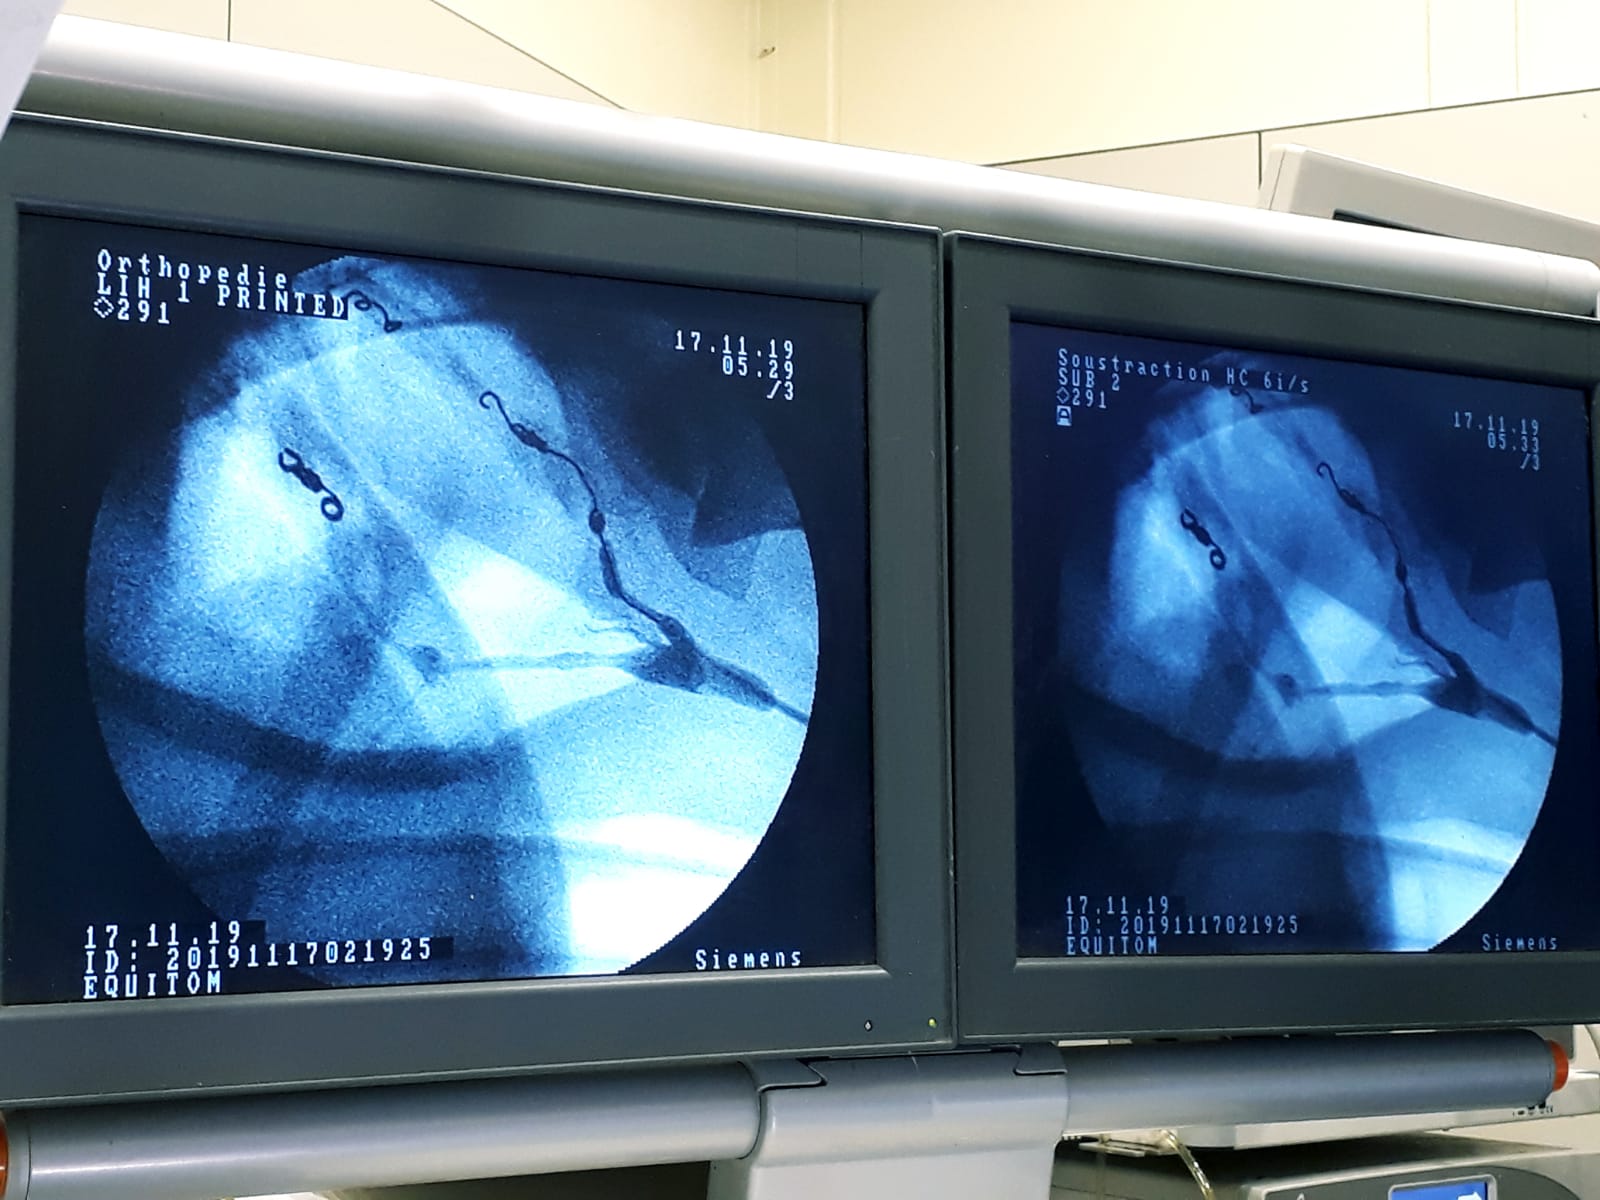

Nejúspěšnější a nejmenšími komplikacemi doprovázená se ukázala technika embolizace (ucpání cévy) pomocí pružiny, kterou využívají veterináři v Equitomu. Původ této metody je v humánní medicíně, konkrétně v radiologii. Zákrok se provádí pomocí katetru zaváděného krkavicí do postižených tepen (obr. 6).

To zahrnuje aplikaci kontrastní látky do tepny a použití speciálního zobrazovacího přístroje (fluoroskopu). S jejich pomocí je možné nalézt cestu k poškozené cévě. Do poškozeného místa se pak katetrem zavede speciální pružina, která napadenou cévu ucpe (obr. 7).

Tyto pružiny se umísťují do nejvyššího a nejnižšího místa vzdušného vaku tak, aby se zabránilo jak běžnému, tak zpětnému toku krve do všech velkých tepen, které procházejí stěnou postiženého vzdušného vaku.

Tato elegantní metoda výrazně snižuje čas potřebný k operaci ve srovnání se staršími technikami, je minimálně invazivní a velmi účinná. Vyžaduje ale zkušenost, přesnost a speciální vybavení.